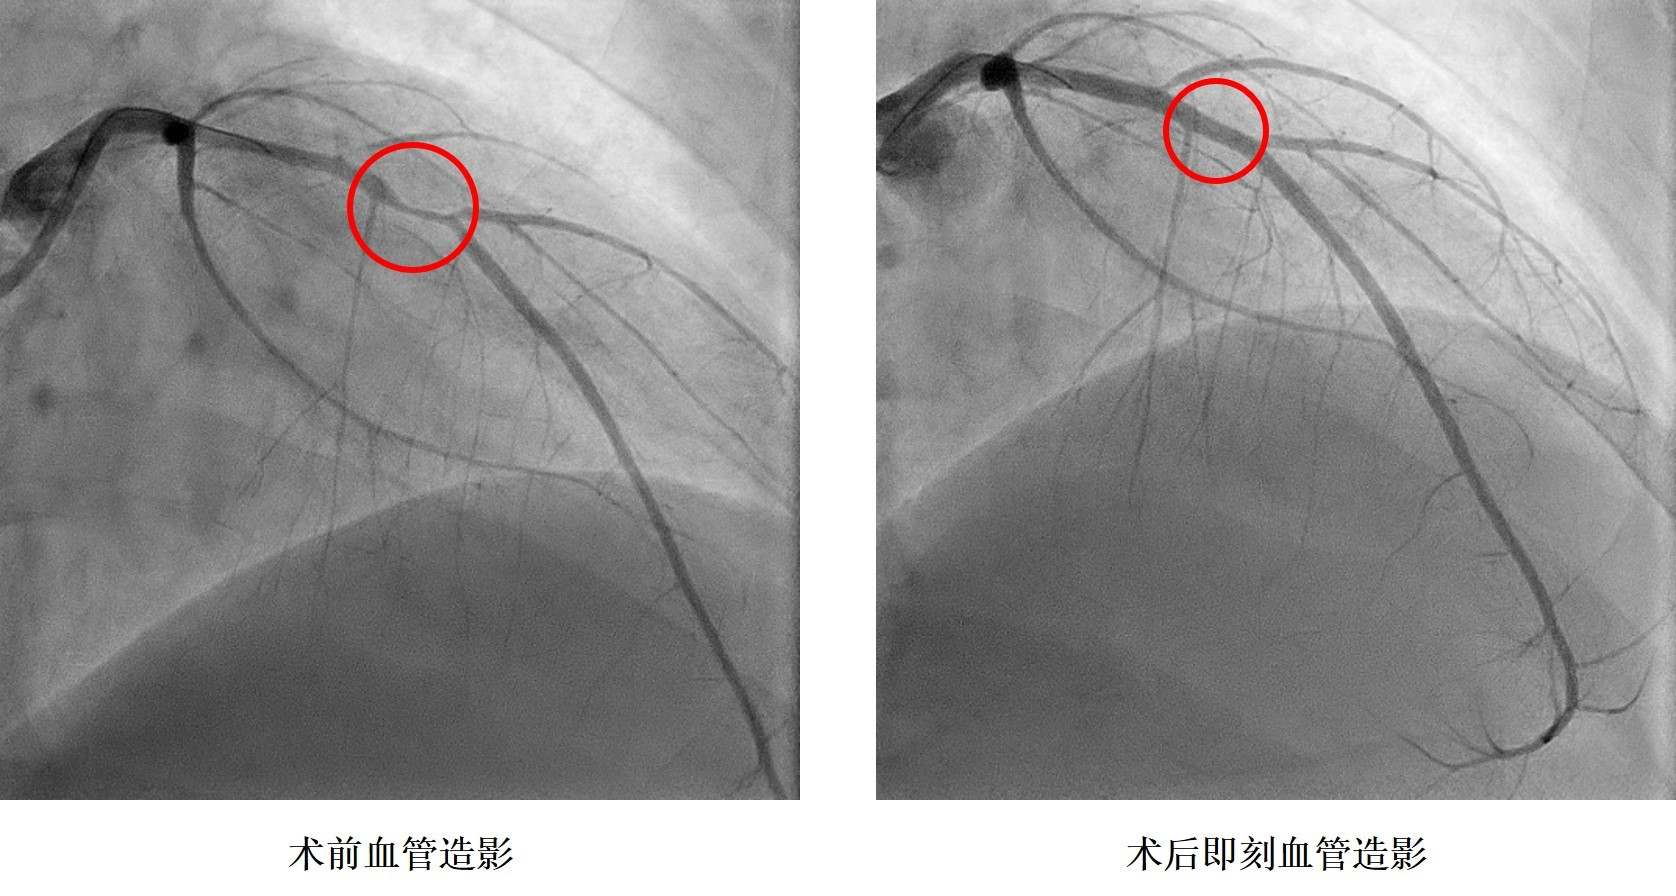

小浩在2019年9月6日晚飯時突感胸痛、胸口悶、呼吸困難,立即前往湖南省人民醫(yī)院胸痛中心就診,診斷為急性心肌梗死,小浩被送往介入手術室,進行急診造影后發(fā)現冠狀動脈血管嚴重狹窄,需要在體內植入心臟支架。據了解小浩從14歲就開始了抽煙,還發(fā)現了高血壓,血壓最高200mmHg,卻一直沒有規(guī)律服藥治療。16歲讀完技校后的他開始過上了淘寶電商的生活,生活日夜顛倒,夜間修圖、改片,并頓頓燒烤,白天睡覺,缺乏運動,這樣的生活維持了兩年本次。入院后同時發(fā)現了糖尿病,這一系列原因是導致小浩發(fā)生心肌梗死的罪魁禍首。

孩子還這么小,人生剛剛開始就要帶上心臟支架生活嗎?心內科鄭昭芬主任組織團隊進行了會診,建議植入生物可吸收心臟支架!拔覀儽緛聿辉敢庵踩胄呐K支架,但聽說有一種新型的心臟支架在植入體內后幾年就能降解,就接受了。”在征得小浩本人和家人同意后,心內三科潘宏偉主任利用血管內超聲指導,順利植入生物可吸收心臟支架,拆除了小浩體內的“炸彈”。